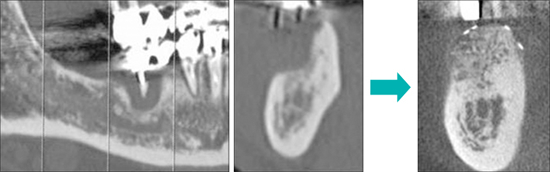

【人工骨と下顎骨による顎骨造成例】

【人工骨と脛骨による顎骨造成例】

CT画像では著明な骨吸収が認められた

水平的・垂直的に骨造成